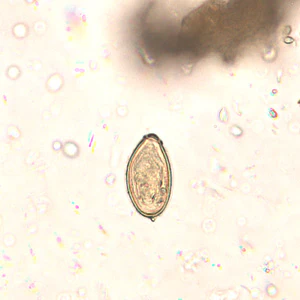

Eggs of Opisthorchis spp. in wet mounts.

Diagnosis is based on microscopic identification of eggs in stool specimens. However, the eggs of Opisthorchis are practically indistinguishable from those of Clonorchis. The adult fluke can also be recovered at surgery.